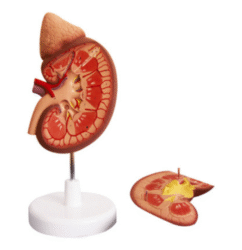

ATL-12 MALE MUSCLES FIGURE 2 PARTS

The model is an anatomically accurate representation of the human anatomy, complete with superficial and deep musculature, the digestive system, lymphatic system, respiratory system, urinary system, circulatory system, endocrine system, and nervous system. Our model has removable organs and dissectible features for a complete educational experience.

Classification:

Skeleton Models(human bone, muscle, etc.)